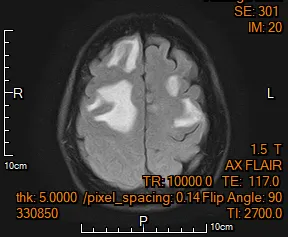

腦幹

頭痛

頭暈

視神經壓迫